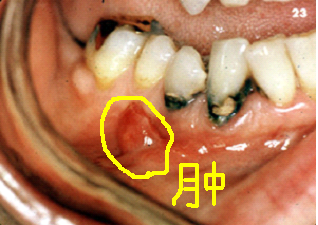

门牙牙髓炎图片,牙髓炎图片开髓

牙髓炎图片开髓

牙髓炎图片

牙髓炎早期图片

牙髓炎图片症状

牙髓炎

牙髓炎症状

牙髓炎的症状